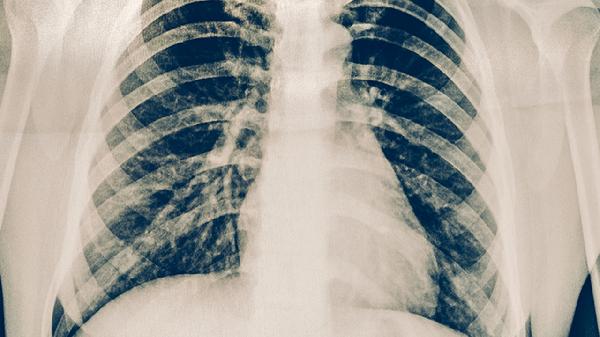

肺部感染或结核可能累及胸膜,导致左侧胸部锐痛,可能与细菌感染、自身免疫疾病等因素有关,通常表现为深呼吸加重、伴发热咳嗽。需行胸部CT明确病因,使用头孢曲松、莫西沙星等抗生素,严重者需胸腔穿刺引流。